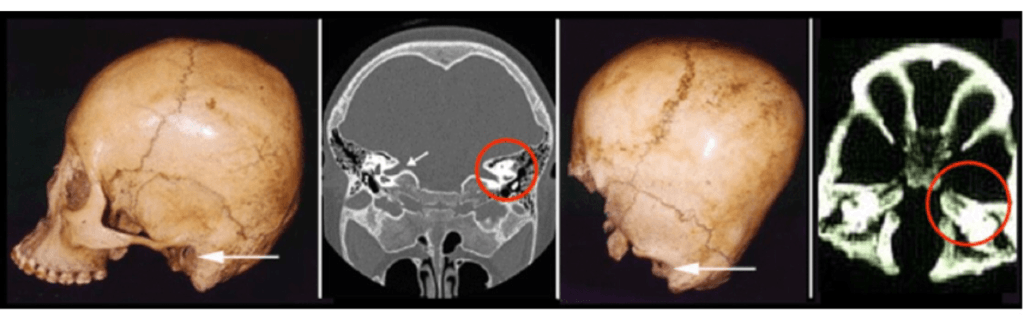

Regular ear canal vs Starchild ear canal

The skull however, showed variations from known mutations and abnormalities like hydrocephaly, such as the lack of the inion region of the skull and the complete flattening of the back of the cranium. Some proposed the theory that the flattening may have come from a practice known as cradle-boarding, though the flattening is significantly more extensive compared to any other skull that had been cradle-boarded. Also, to achieve this level of flattening by cradle-boarding, the child would have been asphyxiated.

The Starchild skull was dated to be 900 years old, while appearing to be around the age of five when it died. Aside from the bulbous cranium, the skull showed shallow, close-set eye sockets that were broken, along with a completely broken and missing jaw. The skull retained its teeth, allowing for an examination from a dentist who helped determine its age.